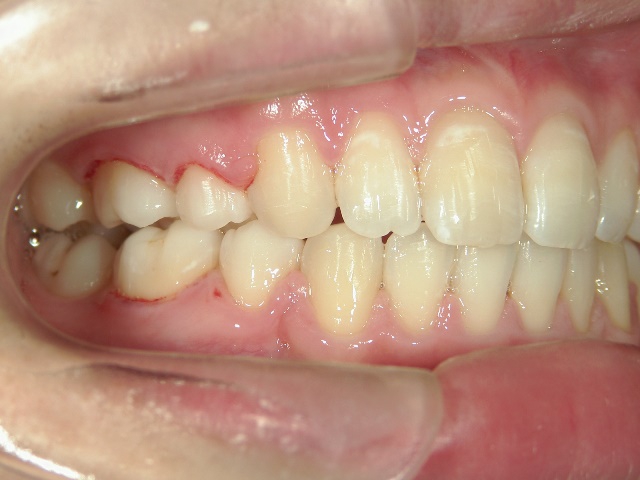

矯正歯科 治療前

全顎ワイヤー矯正 症例(5)

20歳女性 浜松市東区

在住

治療期間2年4

ヶ月